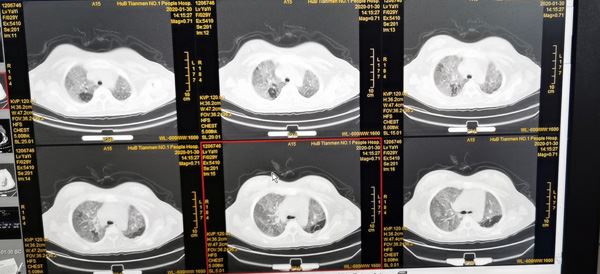

李青的肺部CT。